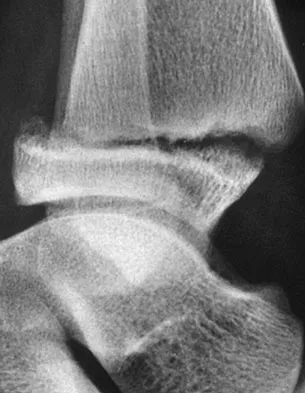

Question 33 High Yield

A 12-year-old boy with an ankle fracture undergoes closed reduction under sedation in the emergency department. Figure 27 shows a lateral radiograph of the ankle after two attempts at closed reduction. Based on these findings, treatment should now consist of

Detailed Explanation